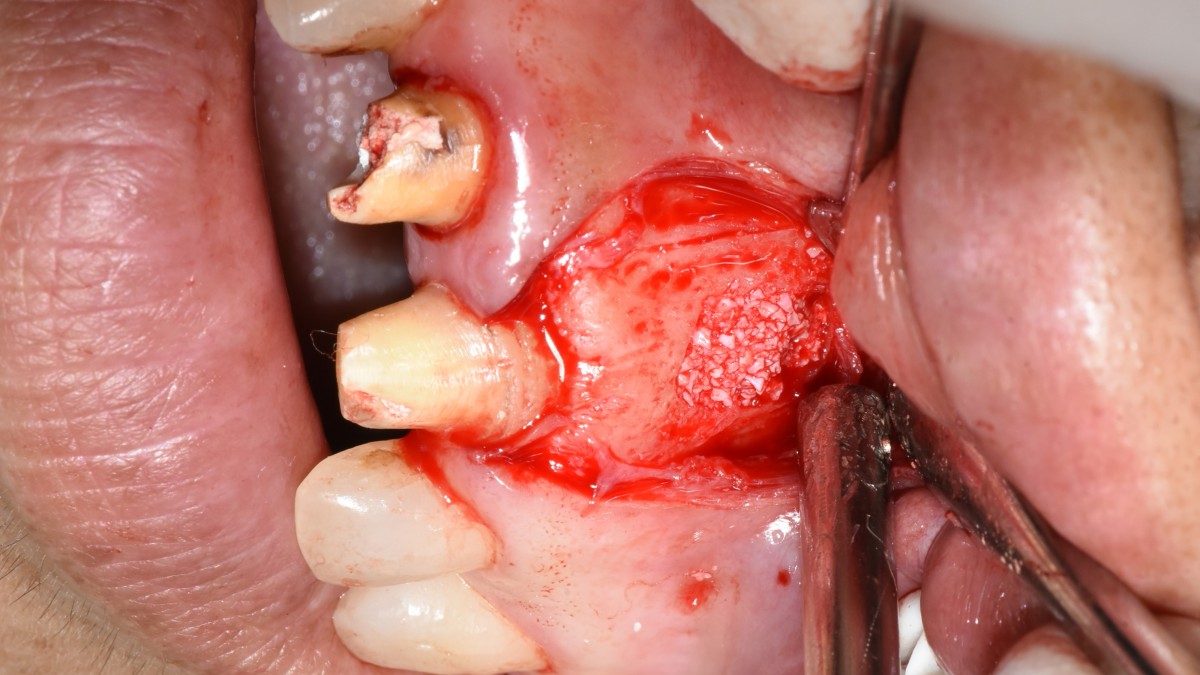

Apicorctomy /central incisor /GBR ; 6-year follow up.

<CJ SBN> Apicorctomy /central incisor /GBR ; 6-year follow up.